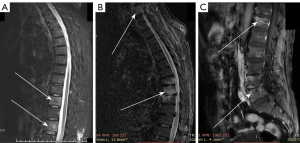

In T1-weighted contrast-enhanced sequences, the occurrence of paravertebral abscesses did not differ significantly across the four groups (Table 5). However, when paravertebral abscesses were present, there was a significant difference among the groups. Epidural abscesses did not show significant differences across the groups. Vertebral intraosseous abscesses, on the other hand, exhibited significant differences among the four groups. In cases where paravertebral abscesses were present, the likelihood of having a large paravertebral abscess was significantly higher in the TS group compared to the other groups (Figure 4). Additionally, vertebral intraosseous abscesses were more prevalent in the TS group than in the other groups (Figure 4).

The two main features of TS are large paravertebral abscesses and vertebral intraosseous abscesses, which are typically multisegmental. These features differ from other types of infectious spondylitis, which tend to form smaller paravertebral abscesses, with a lower likelihood of developing large paravertebral abscesses (7,8). In this study, the presence or absence of epidural abscesses, subligamentous spread, and paravertebral abscesses were not effective indicators to differentiate the four types of infectious spondylitis. While epidural abscesses and subligamentous spread were considered more common in PS, and subligamentous spread was more frequent in TS, a comparative study by Hammami et al. (6) found epidural abscesses to be more prevalent in the TS group than in other types of infectious spondylitis (18,19). Due to data inconsistencies, no conclusive comparison could be drawn from this study, highlighting the need for a comprehensive study involving the four types of infectious spondylitis. Ultimately, these features were not distinguishable among the four types of infectious spondylitis in our study.